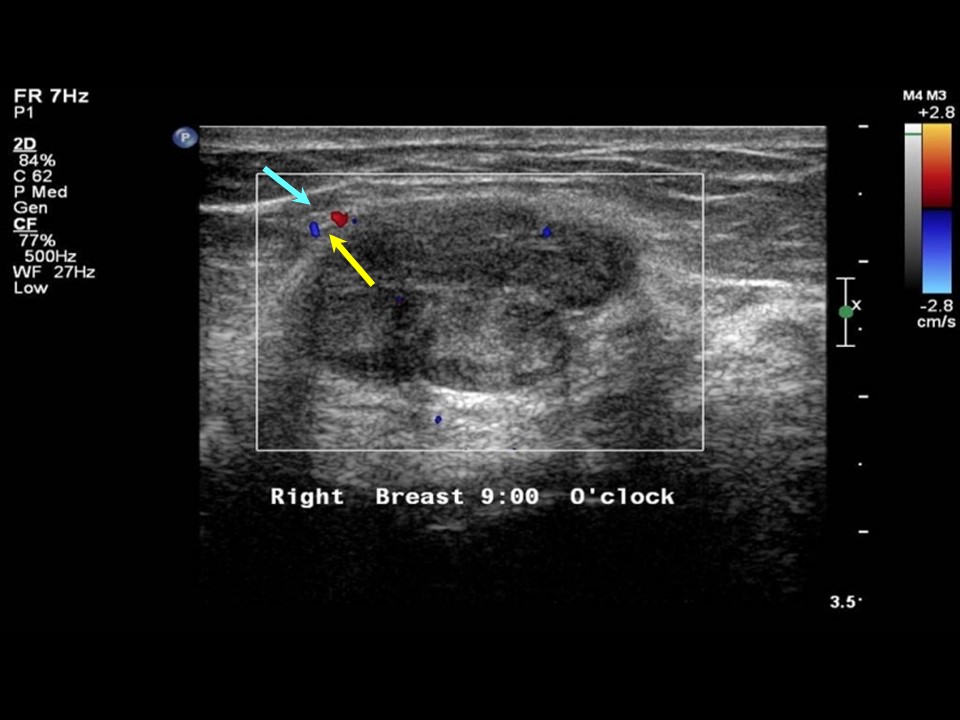

From www.researchgate.net

Ultrasound imaging of the right breast showing 9 o'clock hypoechoic Breast Ultrasound Clock Face The clock face location of breast findings is described by imaging a clock on both the left and the right breast as the woman faces the examiner. Begin at 12 o’clock in a sagittal plane with the toe of the probe at the nipple. Findings in the breasts are described by their orientation on a clock face (figure 1). The. Breast Ultrasound Clock Face.